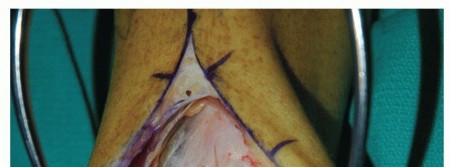

Anterior approach (TECH FIG 6)

Similar to anterior approach for ankle arthrodesis and total ankle arthroplasty Protect the superficial peroneal nerve.

Divide the extensor retinaculum over the extensor hallucis longus tendon. Protect the deep neurovascular bundle.

Anterior capsulotomy, unlike ankle arthrodesis and total ankle arthroplasty, must protect ankle cartilage.

- TECH FIG 5 • A,B. Preoperative radiographs. A. AP and mortise ankle views suggest large medial talar dome OLT and varus alignment. B. Lateral radiograph. C-E. Preoperative CT of largevolume OLT. C. Coronal view. D. Sagittal view. E. Axial view.

Expose OLT with plantarflexion. Assess mediolateral dimensions and attempt to assess AP dimensions.

- TECH FIG 6 • Anterior approach, similar to that performed for total ankle arthroplasty. Because the entire medial one-third to one-half of the talar dome will be restructured, a medial malleolar osteotomy is typically not necessary.